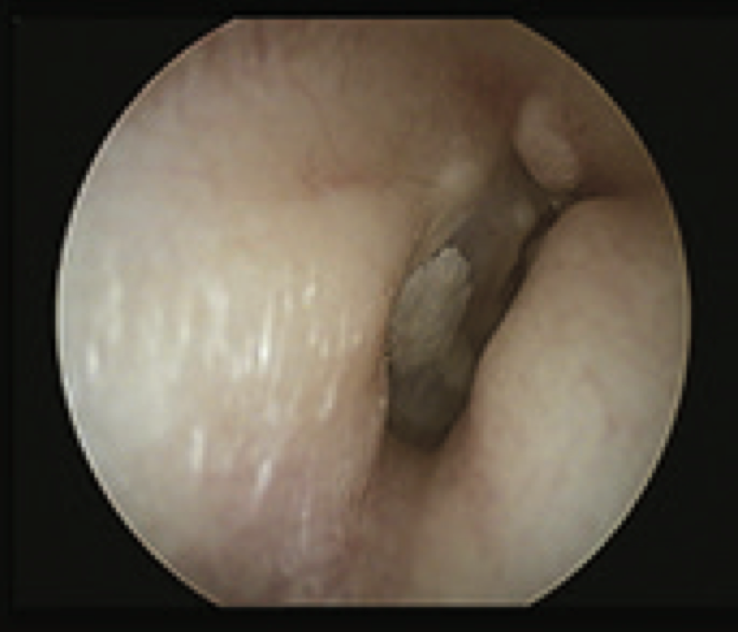

2

Q

What is this?

A

swimmers osteoma

- smooth bony swellings in ear canal

- usually swimmers in cold water